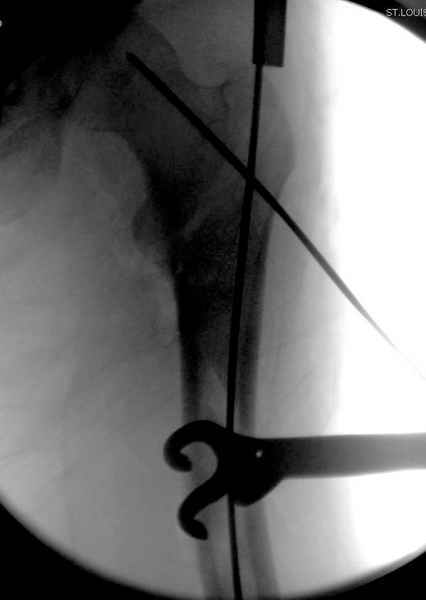

Второй случай тоже репозиция из малого доступа, больному 19 лет, множественные огнестрельные повреждениия конечностей, живота и черепа, правая конечность холодная, без пульсации. Ортопедический диагноз: огнестрельный перелом правого бедра. При срочной ангиографии повреждения сосудов не подтвердилось, конечность из-за ургентности состояния больного зафиксирована временным наружным фиксатором и больной оставлен на операционном столе для срочной лапаротомии хирургической службой.

Больной долго оставался нестабильным, только на 14 день удалось заменить на антеградный интромедуллярный штифт TFN (trochanteric femoral nail) SmithNephew. После неудачной попытки закрытой репозиции, несмотря на использование "joystick", проксимальный стержень от

наружного фиксатора, (перелом начал срастаться) репозицию провели из малого доступа, затем остальные этапы операции.

Случай был представлен из-за того, что больного оперировали после наружной фиксации и был риск инфекцирования через места проведения стержней (на снимках), прошло больше 3 месяцев, выписан из амбулаторной службы из-за отсутсвия надобности дальнейшего наблюдения.